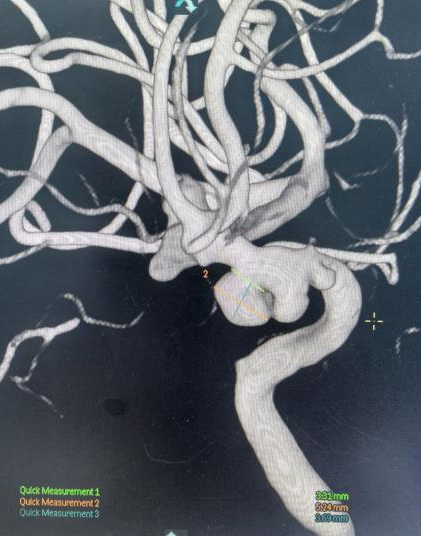

面对大动脉瘤且血管条件差的患者(腹主动脉S型迂曲,右侧颈总动脉II型牛角弓),以及颈内动脉多发动脉瘤的不同患者(C5-C7有5枚动脉瘤),吴全主任团队运用密网支架对症治疗,用一个支架巧妙解决大动脉瘤或多个动脉瘤难题,效果良好,患者短时间内快速恢复。